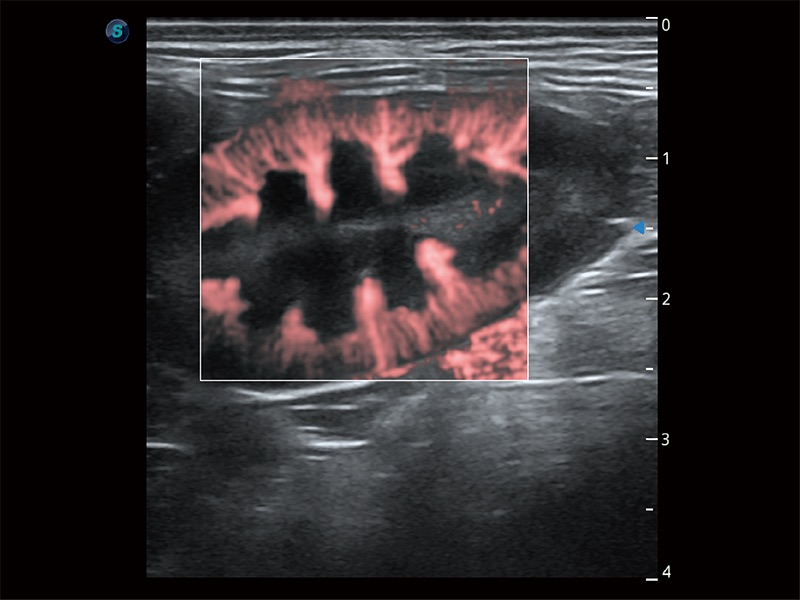

極大提升超低速微細血流的檢出能力,同時更精準地濾除軟組織和超聲信號,為獸用醫(yī)生提供以往無法通過常規(guī)血流獲得的疾病診斷信息。

在傳統(tǒng)二維血流成像的基礎(chǔ)上,呈現(xiàn)血流的立體感,具有動感的生命力之美。即便是微小的血管也能輕松應(yīng)對,提高了血流的視覺敏感性。